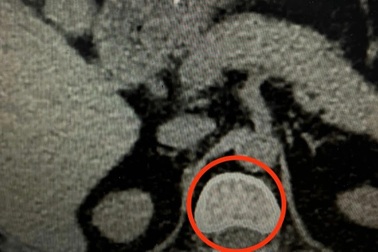

Lạm dụng thuốc giảm đau người thoát vị đĩa đệm dễ tàn phếNhiều bệnh nhân thoát vị đĩa đệm đến khám trong tình trạng lệ thuộc thuốc giảm đau, nguy cơ bại liệt, tàn phế suốt đời. Bác sĩ khuyến cáo cộng đồng không tự ý sử dụng thuốc giảm đau, cần tuân thủ chỉ định điều trị để tránh biến chứng nghiêm trọng.